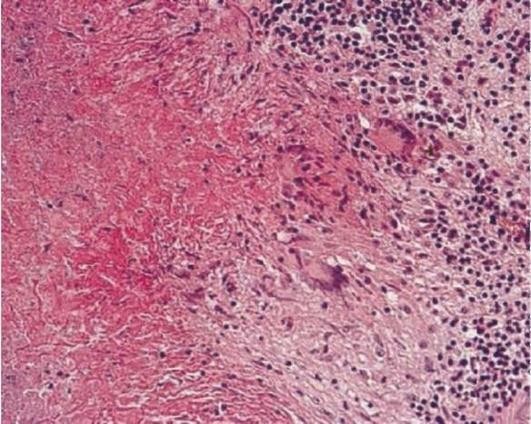

Эпителиоидная саркома

Эпителиоидная саркома 112 фото